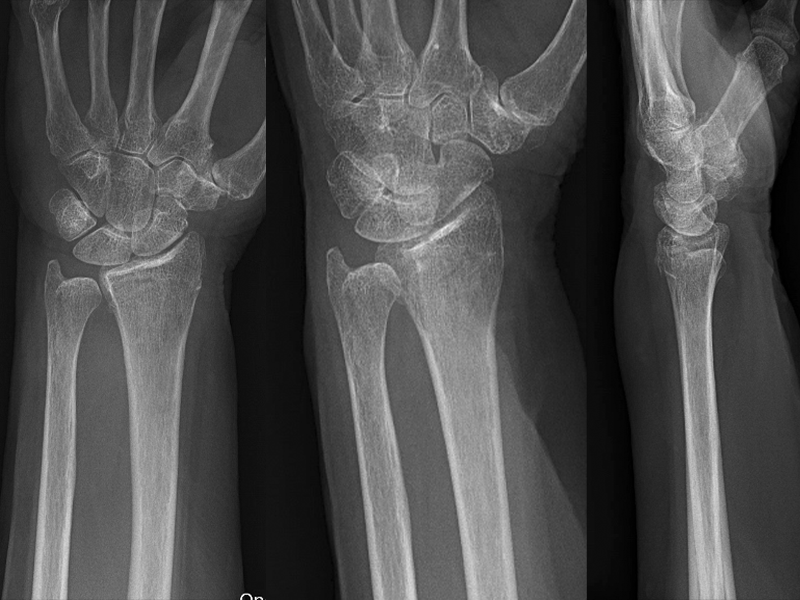

Case 2

Here we see a long axis view of a distal radius on a 79-year-old lady with a fall. In this case, there is a non-displaced fracture, which is actually more clear on the ultrasound than the X-ray. This fracture is clearly not angulated.